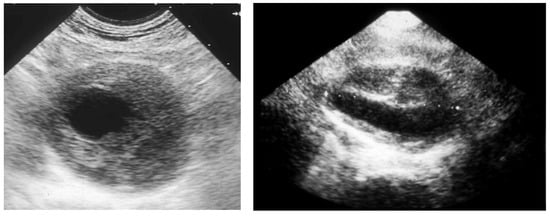

Then, the eventual clinical suspect of an AAA needs to be confirmed or excluded by a first-level investigation, such as a duplex scan, which has a very high specificity (almost 100%) and sensitivity (95%) to detect an AAA (Figure 3) [24].

Figure 3. Duplex scan of the abdominal aorta can easily confirm the clinical suspect of abdominal aortic aneurysm. Short axis (left) and long axis (right) view.